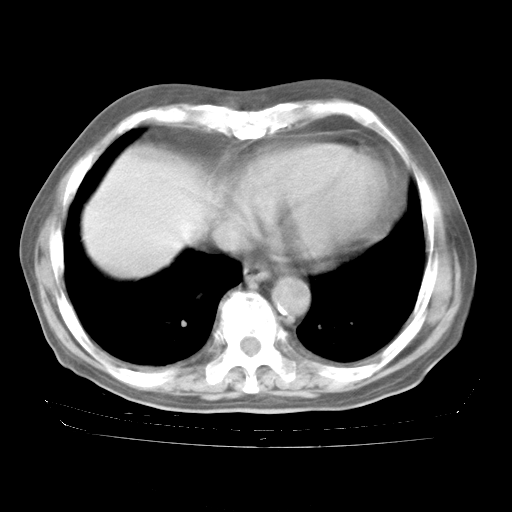

4月28日肺部CT——再次出现类似去年5月9日——透光度降低,“间质性”改变。

个人阅读4.14日肺部CT平扫:纵隔窗无异常,但肺窗示:双下肺内、后基底段有片絮状侵润影,部位以后基底段为著,以间质改变为主,呈急性肺泡炎征像,和首次住院影像学有相似之处。仅是个人读片,明日请相关专家再读片哈。其它建议同上。

今请临免主任会诊后认为:4月14日胸部CT已有双下肺间质性改变。患者病情复发多系激素减量过快不正规所致。目前甲强龙80mg/日,一周后酌情开始减量,不易过快。环磷酰胺若已停用,暂不使用。他同意目前抗菌药物使用,但应考虑是否加用B-内酰胺类抗菌药物(中性细胞明显增高);2、结核复发目前依据不足;3、若免疫全套各项指标正常,考虑多系特发性肺间质炎可能大。4、加强支持,并注意保护胃黏膜。